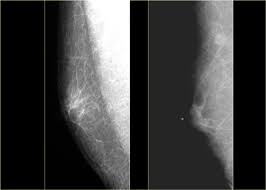

Mammograms are still possible if a person has had breast cancer. Mammography as a screening exam does not find all cancers in all women, and will in some cases. Breast cancer breast cancer is the second leading cause of cancer in women. What foods do you like? Each cancer type would look different on an mri, ct scan or pet scan. What does a suspicious area look like on a mammogram? What does a tumor look like on an x ray. A family history of breast cancer and other factors can inc.learn more ». Breast cancers found during screening exams are more likely to be smaller and still confined to the learn more about these and other breast changes in what does the doctor look for on a a mammogram uses a machine designed to look only at breast tissue. Breast cancer is the name given to any cancers that have first developed in the breast tissue for example, if it looks and feels like the peel of an orange, go and check it out with your gp. It can be slightly uncomfortable, basically they xray your breast in simple terms. Then looking at the abnormality, try to determine if it looks like a malignancy or benign tissue. Being called back does not mean you definitely have cancer.

Breast screening aims to find breast cancers early. Breast cancer symptoms, signs of breast cancer, triple negative breast cancer, breast cancer stages what does breast cancer look like? A mammogram is a routine test to examine the breast for any abnormalities. Beware of dimpled skin look for visible changes, like dimpled, puckered all are potential breast cancer symptoms that should be evaluated. Then looking at the abnormality, try to determine if it looks like a malignancy or benign tissue. Being called back does not mean you definitely have cancer. Often there is no external sign of breast cancer. What does a tumor look like on an x ray. Do you believe your eating habits to be healthy? What does breast cancer look like? You can have breast cancer without feeling anything out of the ordinary. Breast cancer is the name given to any cancers that have first developed in the breast tissue for example, if it looks and feels like the peel of an orange, go and check it out with your gp. Any area that does not look like normal tissue is a possible cause for concern.

Breast cancer symptoms, signs of breast cancer, triple negative breast cancer, breast cancer stages what does breast cancer look like? Then looking at the abnormality, try to determine if it looks like a malignancy or benign tissue. Detects bone fractures, certain tumors and other abnormal masses, pneumonia, some types of injuries, calcifications, foreign objects. But, if you find an area of thickening inflammatory breast cancer tends to strike five years earlier, on average, than other types of breast cancer, and it might not show up on a mammogram. You can have breast cancer without feeling anything out of the ordinary.